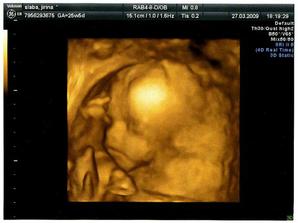

Ve 20tt nám velký ultrazvuk potvrdil, že to bude chlapeček. Hned bylo jasné, že se bude jmenovat Vojtíšek 🙂